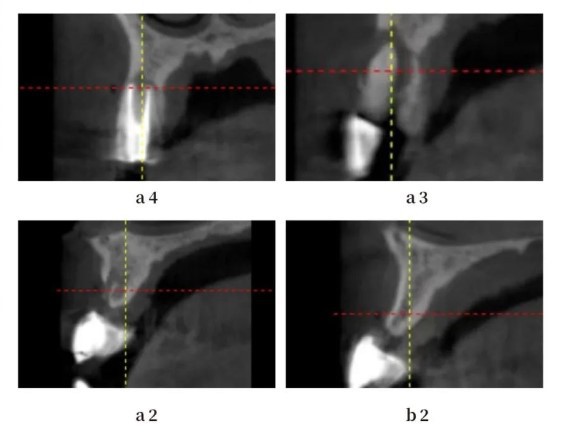

Extensive bone destruction is observed in A3, leading to bone deficiencies in A4 and A2.

Due to bone deficiency in the distal aspect of A2, the design is modified to place the implant in the A1 region, avoiding the area of bone deficiency.

Extensive bone destruction is observed in A3, resulting in bone deficiencies in A4 and A2.

It is observed that the buccal-lingual bone width is adequate in the A1 region.

It is observed that the buccal-lingual bone width is adequate in the B2 region.